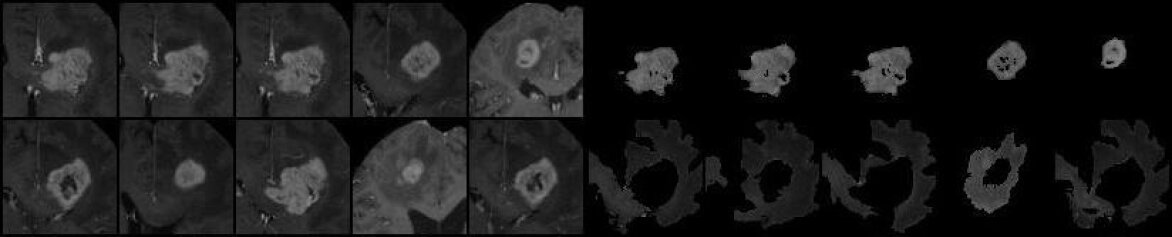

For the out-of-distribution bio-medical image dataset, we assemble three sets of radiological images featuring 6 organ/lesion concepts. These images are sourced from three public MRI segmentation datasets: heart myocardial infarction (Lalande et al., 2020), prostate segmentation (Antonelli et al., 2022), and Brain Tumor Segmentation (BraTS) (Menze et al., 2014). Each dataset includes per-concept masks. For biomedical images, we request a human or a machine, such as GPT-4, to similarly describe each image using one adjective and one noun for each pertinent concept. For both natural and biomedical datasets, we collected 40 images for each concept. Figure 43 and Figure 44 gives some examples of the prepared datasets.

![]() |

| hamster (top) - watermelon (bottom) | cavity (top) - myocardium (bottom) |

| bananas (top) - basket (bottom) | transition (top) - peripheral (bottom) |

| cactus (top) - ball (bottom) | tumour (top) - edema (bottom) |